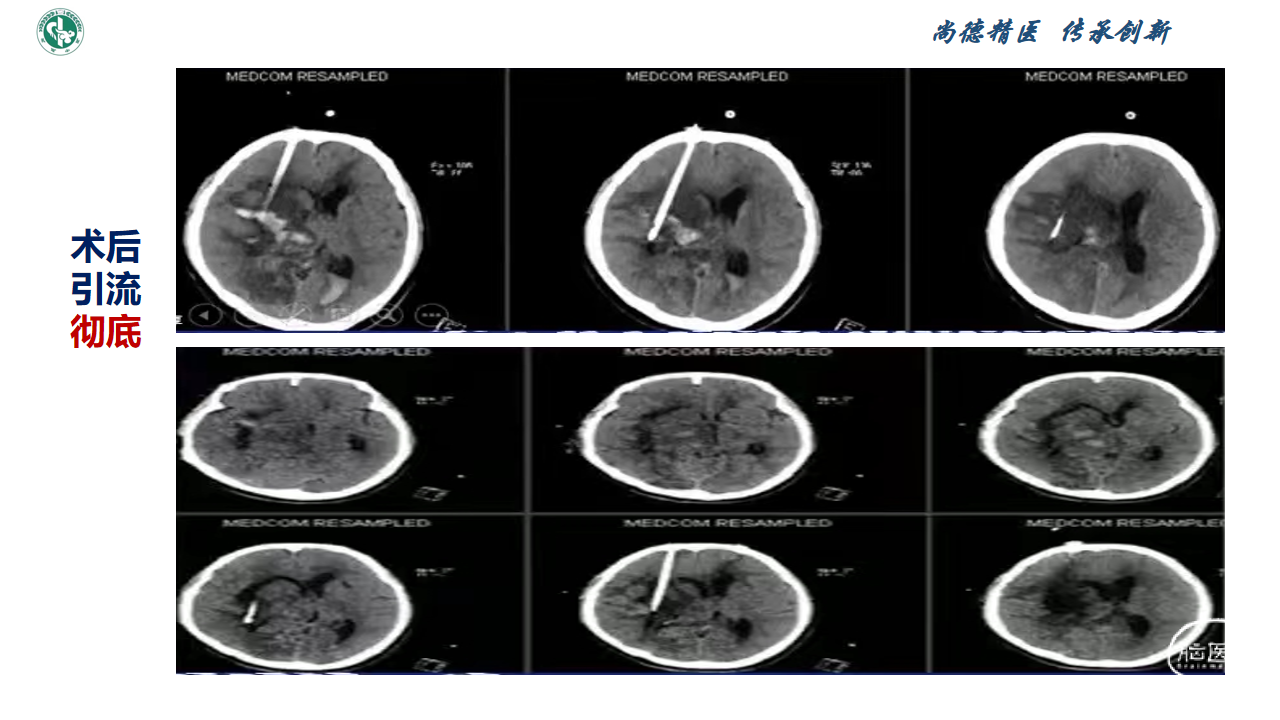

新技术|脑出血微创锥颅软通道引流理念

赵宝元

武威市中医医院